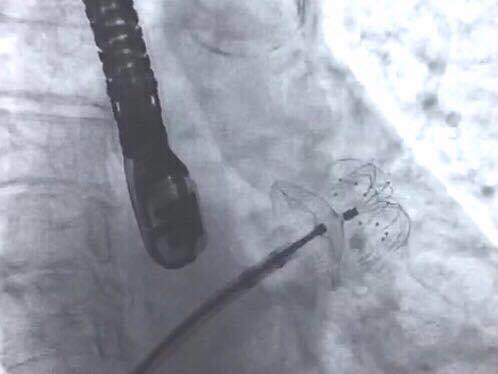

手术选用型号为2430的LAmbre™左心耳封堵器

当日接受手术的患者为一名74岁女性,伴有高血压,脑卒中,心律失常。入院评估CHA2DS2-VASc 评分为3分,HAS-BLED评分为4分。术中造影测量左心耳大小,锚定区测量结果为19.6±2.8mm,开口部区域测量结果为22.0±2.2mm。陶凌教授与其团队讨论后,决定选用彩神在线网信彩票-彩神通免费版下载-彩神8争霸vlll-彩神购彩购彩大厅-彩神软件陆立根免费版-彩神ll争霸3-彩神ll彩神8-彩神ll争霸彩票-拼搏在线彩神网网页版科技自主研发的LAmbre™左心耳封堵器系统2430型号的封堵器进行手术封堵。术后经造影对比及超声结果显示手术封堵效果出色,患者左心耳封堵完全,无残余分流。陶凌教授对此次LAmbre™左心耳封堵器的植入结果表示满意。陶凌教授认为LAmbre™左心耳封堵器系统在术中可轻松实现回收和再释放,便于调整最佳封堵位置,且操作可控,让左心耳封堵手术更安全、简单、有效。